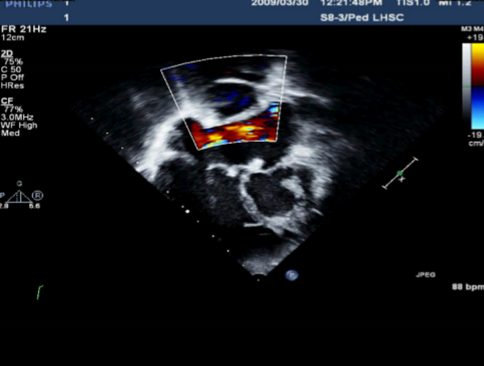

Describe the findings of this image.

Biphasic low velocity flow in a Glenn shunt.

Connection between RPA and SVC.